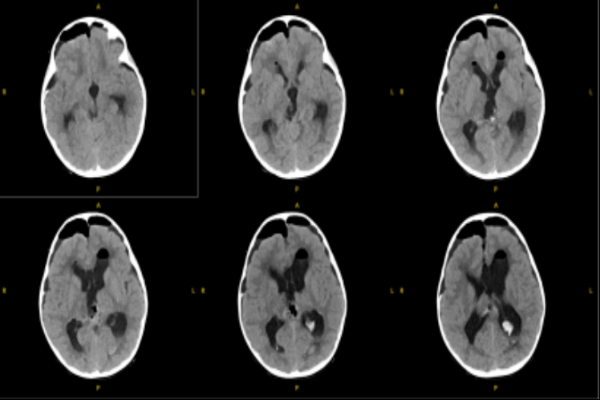

术后病理考虑为颅内间叶源性肿瘤,非脑膜上皮来源。FISH提示EWSR1不典型断裂阳性。术后MRI显示肿瘤完全切除。目前患儿情况稳定,由ICU转入普通病房。

患儿术后MR影像:松果体区肿瘤组织切除完全